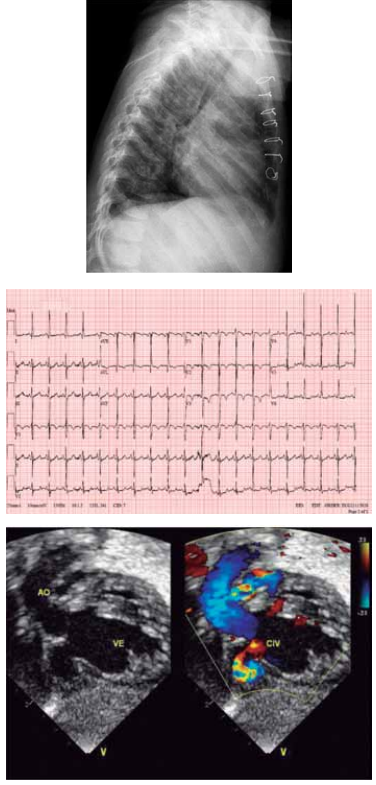

Paciente de 1 mês de idade foi admitido em Unidade de Terapia Intensiva, acompanhada de cuidadora de abrigo, devido à piora da cianose. Mãe drogadita perdeu guarda dos 6 filhos. A saturação na Unidade manteve-se estável, ao redor de 84%, sem insuficiência cardíaca congestiva, em uso de propranolol; foi acompanhado no ambulatório até os 2 anos de idade e realizada intervenção cirúrgica cardíaca. Com base nos seguintes exames complementares, quais seriam, sucessivamente, a cardiopatia congênita provável, a cirurgia realizada aos 2 anos de idade e a cirurgia atual para a qual foi convocada?

(Arquivo pessoal; imagens usadas com autorização)